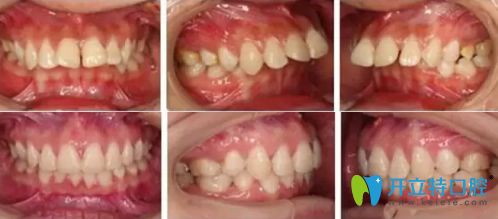

廣州廣大口腔這個(gè)19歲姑娘矯正上下牙齒擁擠中線不齊,只用了一年半時(shí)間

這個(gè)19歲姑娘矯正上下牙齒擁擠中線不齊,只用了一年半時(shí)間

你知道19歲矯正牙齒要多久嗎?這個(gè)19歲的小姐姐在廣州廣大口腔矯正牙齒擁擠不齊,只用了一年多的時(shí)間哈。